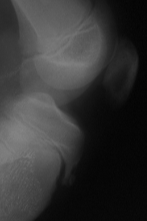

Bei dem Morbus Schlatter handelt es sich um eine Erkrankung, welche bei Jugendlichen im Alter zwischen 14 bis 16 Jahren abläuft. Es handelt sich um eine Verknöcherungsstörung des Ansatzbereiches der Kniescheibensehne am Schienbeinkopf. Der Ansatzbereich der Sehne verwächst nicht mit dem Schienbein, so daß hier ein isolierter Knochenkern bestehen bleibt.

Dies führt zu einer Verdickung, welche bei stärkerer sportlicher Belastung und insbesondere beim Knien schmerzhaft sein kann.

Die Diagnose wird gestellt durch den typischen lokalen Untersuchungsbefund und ein Röntgenbild.

Schlatter DSCF3331